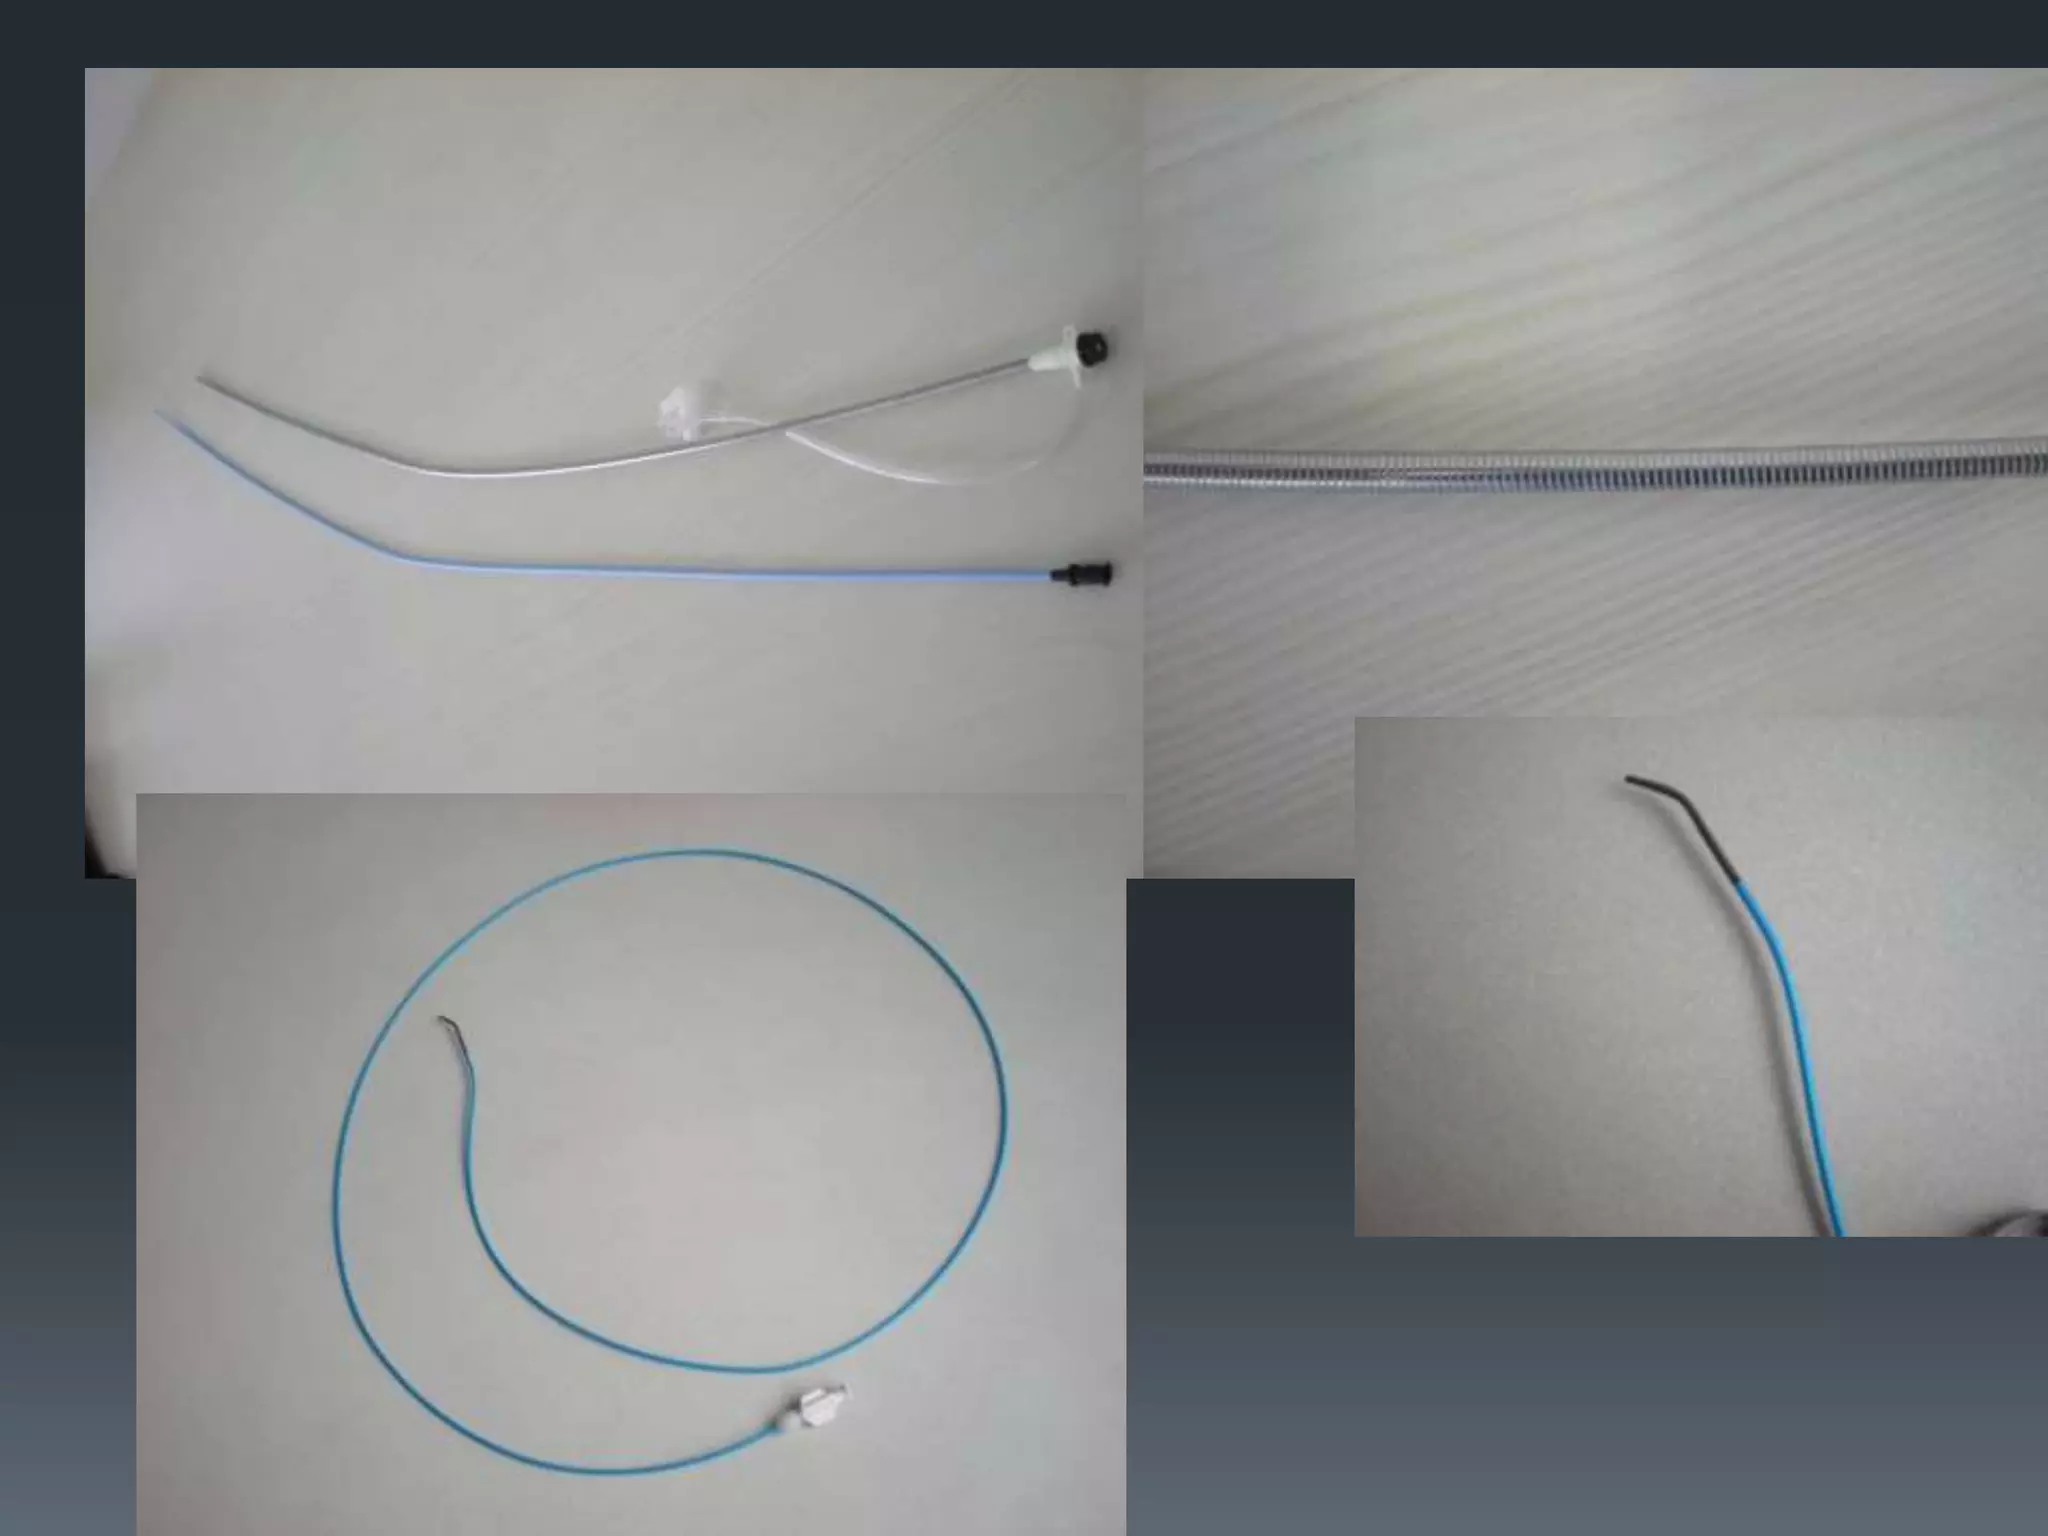

This document discusses tricks and techniques for difficult cannulations during neurointerventional procedures. It outlines strategies for accessing the aortic arch, internal carotid artery (ICA), and areas distal to aneurysms. Long sheaths, distal access catheters, and co-axial techniques are presented as options that have improved cannulation success. Guidance on sheath and catheter selection is provided for different vessel paths. The importance of catheter placement as high as possible in the ICA is emphasized. Reverse curve cannulations are also mentioned. Overall, the document stresses that careful cannulation is critical for procedural success and different strategies may be needed depending on the vessel target.